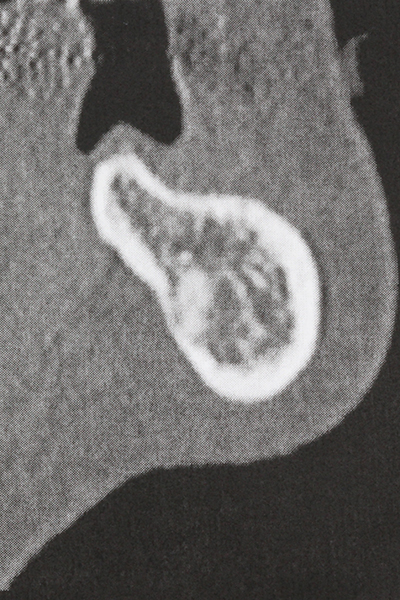

Bone tissue is not simply a mineral structure but also contains a substantial proportion of collagen fibres. This means it not only has good compressive strength but also a degree of flexibility, which can be taken advantage of when performing bone augmentations. In the classical expansion procedure using bone splitting, the atrophied alveolar ridge is split longitudinally and carefully expanded after reaching an adequate osteotomy depth (Fig. 13-16), ideally without substantial removal of the periosteum (Brugnami, Caiazzo et al. 2014, Stricker, Fleiner et al. 2014). Screw and plate systems with increasing expansion distance have proven effective in separating the two bone lamellae while remaining below the fracture threshold. In general, residual bone widths of at least 3–4 mm are required (Chiapasco, Zaniboni et al. 2006) to guarantee adequate flexibility and sufficient bone coverage of the future implants. If necessary, a vertical relief osteotomy on one or both sides can improve flexibility. A combination with additional augmentation techniques, particularly on the buccal side, has been described as an alternative to the classical technique.